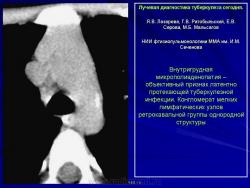

Лучевая диагностика туберкулеза сегодня

Я.В. Лазарева, Г.В. Ратобыльский, Е.В. Серова, М.Б. Мальсагов

НИИ фтизиопульмонологиии ММА им. И.М. Сеченова